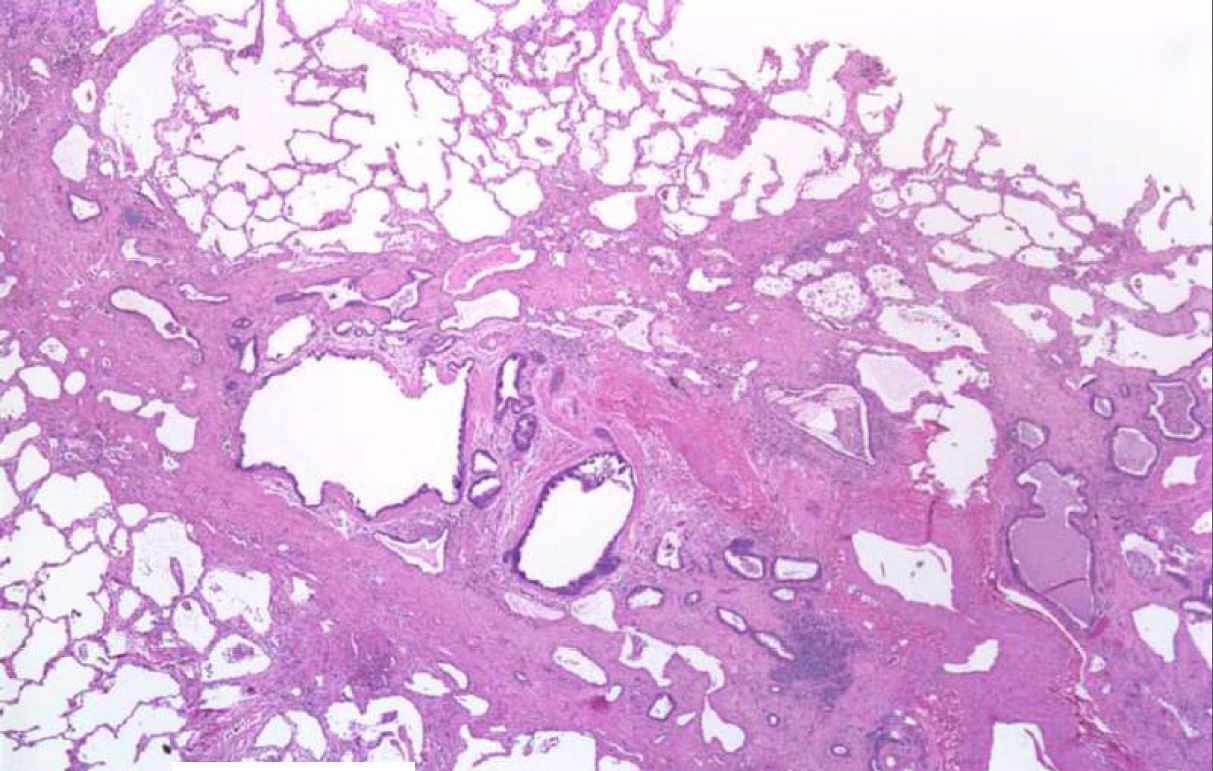

What process is being shown here?

Hallmarks are lower lobes and peripheral/paraseptal

accentuation of changes

UIP